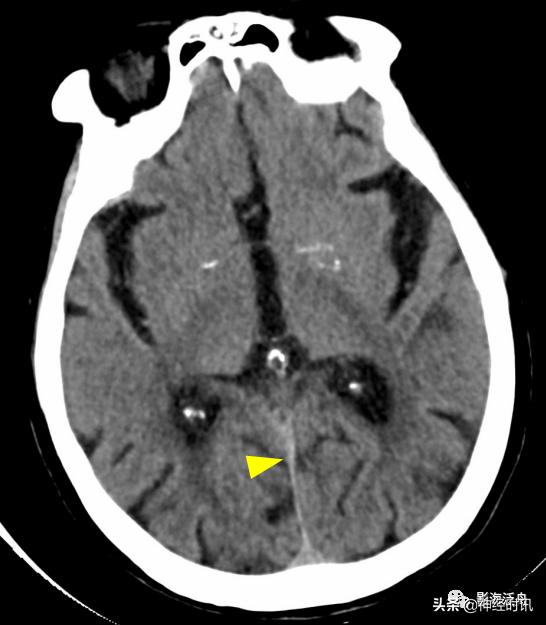

部分国外学者认为少量蛛血的常见部位位于大脑中脚之间的脚间池内(红箭),笔者尚未遇到过(是不是漏掉了?)。此种类型的少量蛛血常可引起患者“雷击样头痛”,且血管造影几乎均为阴性,如果在急诊CT平扫中漏诊此型蛛血,将会对临床诊断造成极*麻大**烦,因为可逆性血管收缩综合征等也会出现类似的剧烈头痛症状。